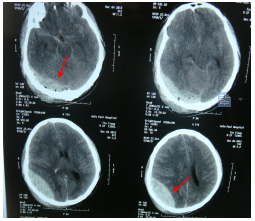

2.审查某市医院病历:某市医院某号住院病历记载:刘某于某年12月4日晨5时许因头部外伤半小时入院。入院检查:神清,嗜睡,自诉头痛,并向护士告知家庭住址及电话号码。双瞳孔等大等园,对光反射灵敏。12月4日5时54分头颅CT扫描提示: 右枕骨骨折,右枕部少量硬膜外血肿,左颞部硬膜下小血肿,蛛网膜下腔出血;给予脱水、止血、激素等药物治疗。入院50分钟后,意识障碍逐渐加深至昏迷。当日12时50分行第二次头颅CT复查。报告:右顶枕部大片状高密度影,同侧脑室、脑池受压、脑沟消失,中线结构左移,提示右枕顶部硬膜外血肿明显扩大伴脑疝形成,右顶枕骨骨折伴外伤性气颅,蛛网膜下腔出血,脑肿胀。立即送手术室准备开颅手术。麻醉前呼吸心跳聚停,紧急作心肺复苏,同时开颅血肿清除,去骨瓣减压。但呼吸循环功能仍未能恢复,当日14时宣布临床死亡。死亡诊断:右颞枕顶部硬膜外血肿,脑疝形成。

3.请上级医院专家阅片会鉴记载:某年某月6日,刘某家属请省级医院影像科教授会鉴某市医院某年12月4日12时50分刘某生前头颅CT片,阅片会鉴诊断:①外伤性蛛网膜下腔出血;②外伤性脑肿胀与弥漫性轴索损伤;③右顶后硬膜外血肿;4.右顶骨骨折;5.右大脑镰下疝。

某年12月4日12:50分,刘某入院6小时后CT显示